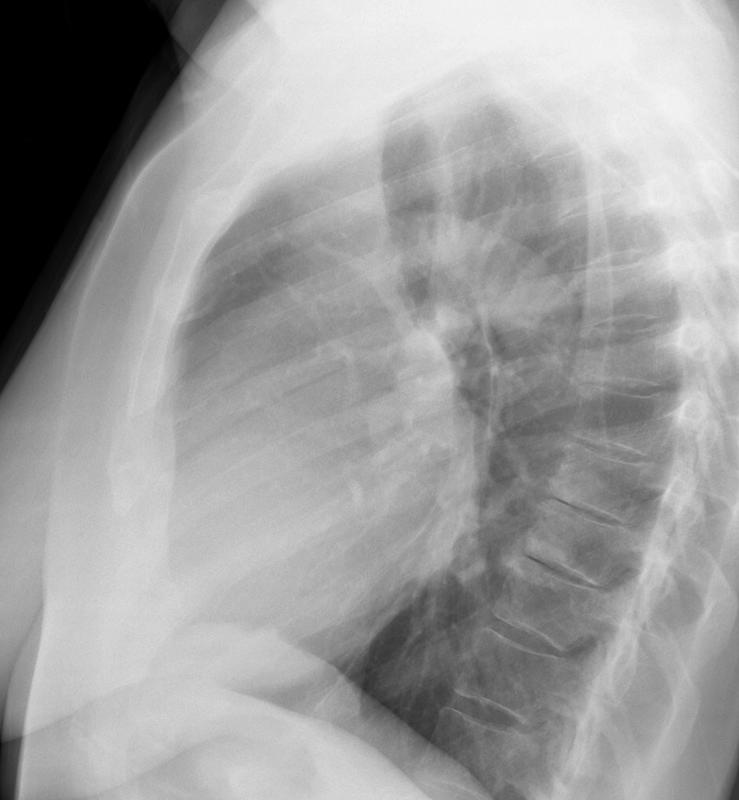

Gallery Cardiac Mitral Valve Disease Mitral Valve Disease Case 10 Lat

Mitral Valve Disease

Case 10 Lat